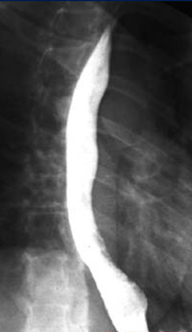

| images TOGD de oesophage

normale |

- A oesophage s'il n'a pas des

lesion de retrecie , la produit de contrast baryte de

ingestion doit etre en pâte

et les cliches exposes doient prenes en face , en OAD ou

OPG . Le trajet de oesophage soit rectiligne et y avait

trois segment : cervicale , thoracique et abdominale . La contraction de oesophage peut etudier

par analyse dynamique en scopie televisee .

Le passage de

la contenue a traverse au long de oesophage avait

perdu de 5 a 7 seconde . Sur oesophage a contrast

baryte normale il y avait trois region serre physique de la

lumeniere de l'oesophage :

- Au superieure , c'est empreinte du

bouton aortique . Le passage de la contenue est

lente et traverse cette serre en 1/2 a 2 seconde

- A inferieure c'est l 'empreinte du

bronche souche gauche et empreine de oreillete

gauche

- A tranverse de diapragme , a

hauteur de D10 c'est le retressisement de hiatus

oesophagien . La contenue de oesophage se

ralentir et arrete de 3 a 5 seconde |

Les plies muqueuse de oesophage sont

longitudinale et bien visible sur les cliches

obtenus en faible de remplisage et disparaissent en

distension . |